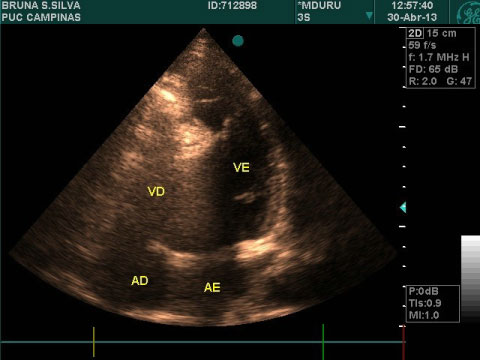

Due to investigation, the patient presented with a simple x-ray of the chest (Figure 1) an increase of the cardiac area in posterolateral projection. An echocardiogram showed measurements of normal cardiac chambers, walls and ventricular function. An extrahepatic, homogeneous structure was identified, with minimum measurements of 13 × 13 mm, with infiltration of the interventricular septum, adhered to the pericardium, with increased refraction leading to cardiac displacement (Figure 2).

Figure 2: An echocardiogram showed measurements of normal cardiac chambers, walls and ventricular function. View Figure 2